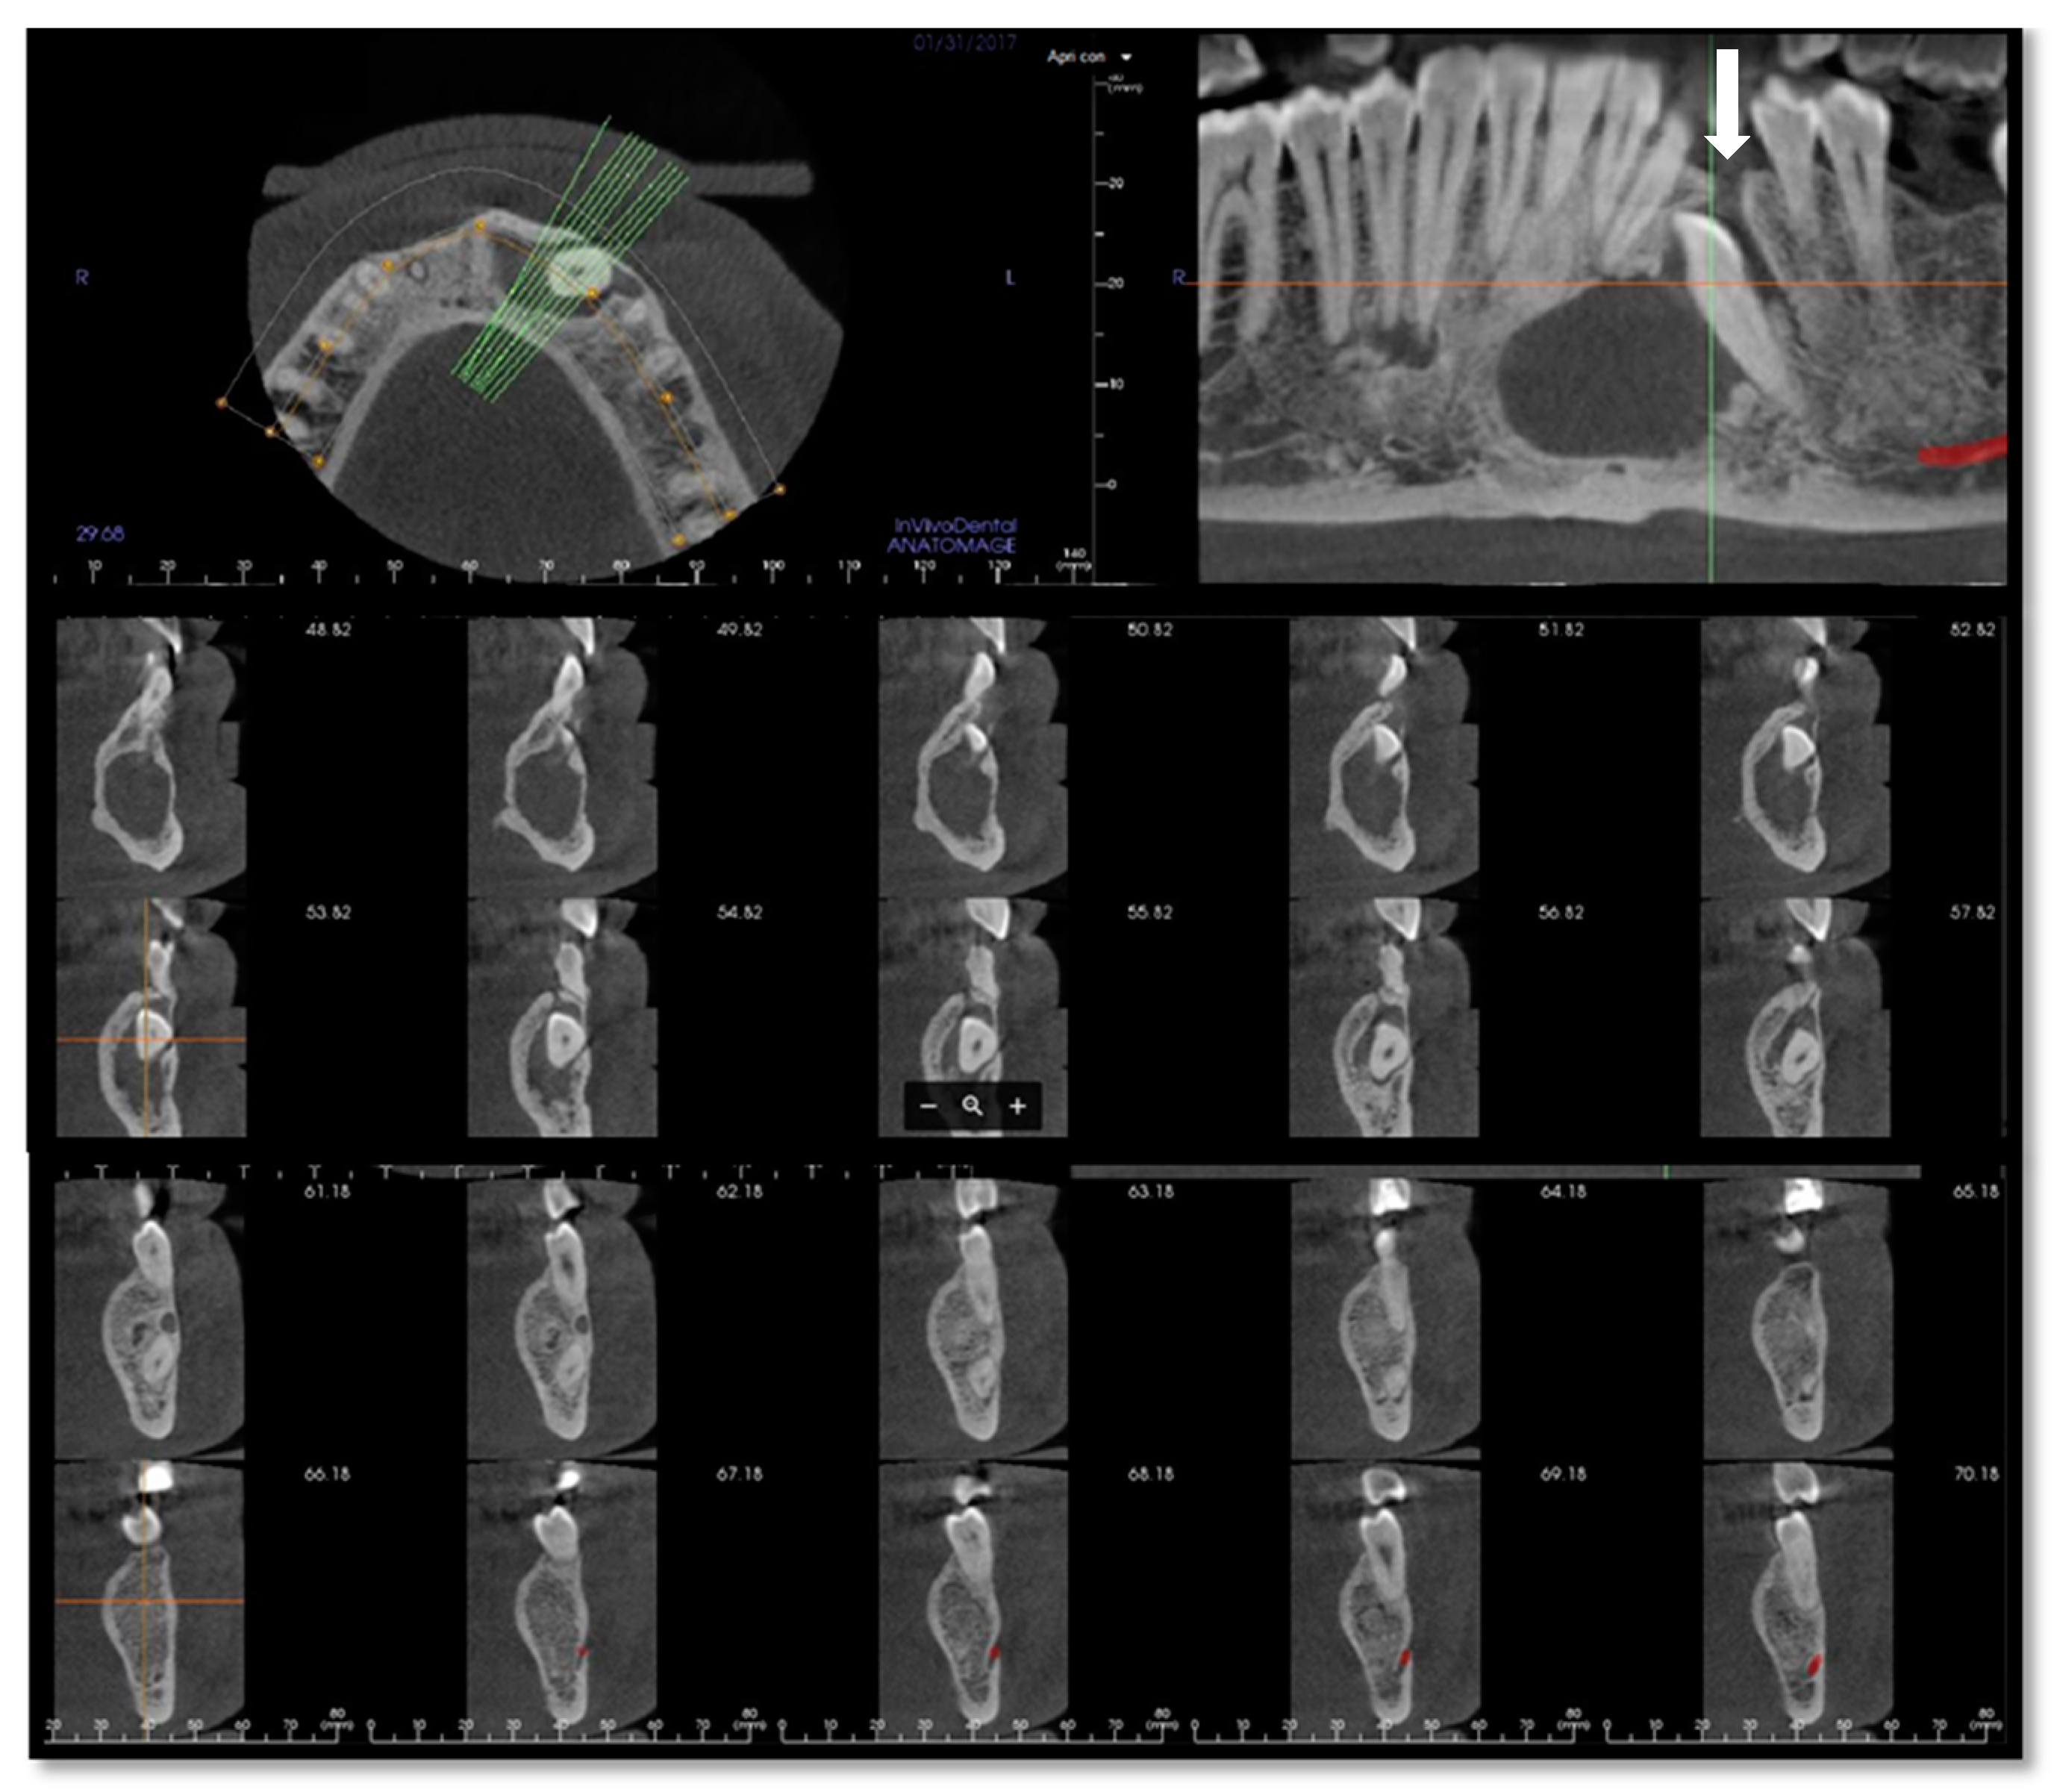

Figure 2.

Cone-beam computed tomography (CBCT) of the mandible performed in January 2017 after the first infective episode and showing no atypical radiologic findings. The osteolytic alveolar defect (white arrow) has led to the recurrent oral discharge.

The radiological appearance of PIOSCC is variable, ranging from well-defined benign-like masses to ill-defined osteolytic lesions [,]. The most common imaging presentation is a radiolucent cup or dish-shaped osteolytic bone lesion, followed by diffuse and poorly defined borders appearance known as ‘moth-eaten’ radiographic pattern []. Kaffe et al. proposed that the presence of indistinct margins without a sclerotic outline may be an important peculiarity of PIOSCC [] (Figure 2). Another significant radiograph characteristic is the lack of root resorption, presumably suggesting that the tumor invasion occurs along the path of least resistance, resulting in a unique pattern known as ‘floating-teeth,’ which is rarely seen in benign odontogenic cysts or tumors [] (Figure 2). Radiopaque foci corresponding to calcifications or dentinoid structures and ground-glass opacity (possibly mimicking fibrous dysplasia or ossifying fibroma) have also been reported by some authors [,].

In our case, orthopantomography (Figure 1) and CT (Figure 2) showed a uniloculated 38 × 14 mm osteolytic area affecting the chin symphysis and extending in the left paramedian region. The lesion interrupted the vestibular bone cortex but spared the lingual one.